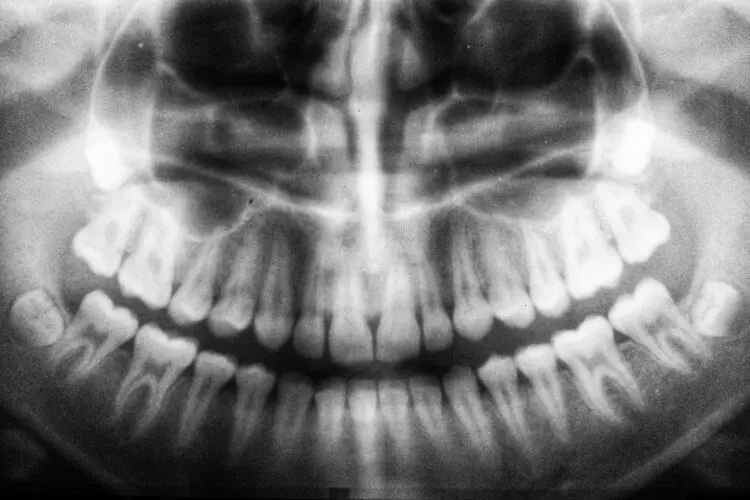

What Do I Do If I Chipped a Tooth?

Chipping or breaking a tooth is nothing to take lightly. In fact, chipping a tooth can sometimes be a dental emergency. If the internal structure of the tooth is exposed, or if you’re in any pain, you should see a dentist urgently. Even if you’re not in pain, a chipped tooth can easily become more